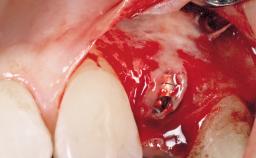

A 30-year-old female patient was referred to the office for the treatment of tooth 11. Her chief concern at the initial visit was to inquire, “Why is my tooth pink?” Upon clinical examination, it was determined that tooth 11 had a previous history of trauma and that the clinical crown had become noticeably pink in color as a result of internal resorption. This diagnosis was confirmed radiographically, indicating a large radiolucency involving the central and distal portions of the clinical crown. It was determined that restoration of this tooth was not possible, and that extraction was indicated. The presence of a mid-line diastema, which the patient wanted to reproduce, directed the treatment plan for tooth replacement utilizing a dental implant.

Placement Protocol Immediate implant placement

Tooth Site Maxillary incisor or canine

Socket Morphology Single-root socket

Socket Integrity Sufficient, with intact bone walls